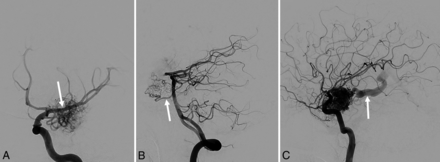

A 19-year-old man was diagnosed with an unruptured 3.5 × 2.9 × 2.5 cm Spetzler-Martin grade III AVM in the medial left temporal lobe on a trauma work-up. Conventional angiography showed primary arterial supply from the left MCA with secondary contribution from the left posterior cerebral artery (Fig 1A, -B). Venous drainage was solely via the left basal vein of Rosenthal (Fig 1C). The nidus was treated with single-fraction SRS to a prescription dose of 1800 cGy (mean dose, 2000 cGy; maximum, dose 2200 cGy) using a linear accelerator–based volumetric arc therapy technique. The patient experienced no acute or subacute complications.

Conventional angiography of a left temporal lobe AVM. Early arterial phases show primarily MCA supply (arrow) on a left frontal oblique left ICA injection (A), with secondary posterior cerebral artery supply via a small branch artery (arrow) on a lateral left vertebral artery injection (B). Late arterial phase (C) shows early opacification of the left basal vein of Rosenthal, the exclusive venous drainage (arrow).